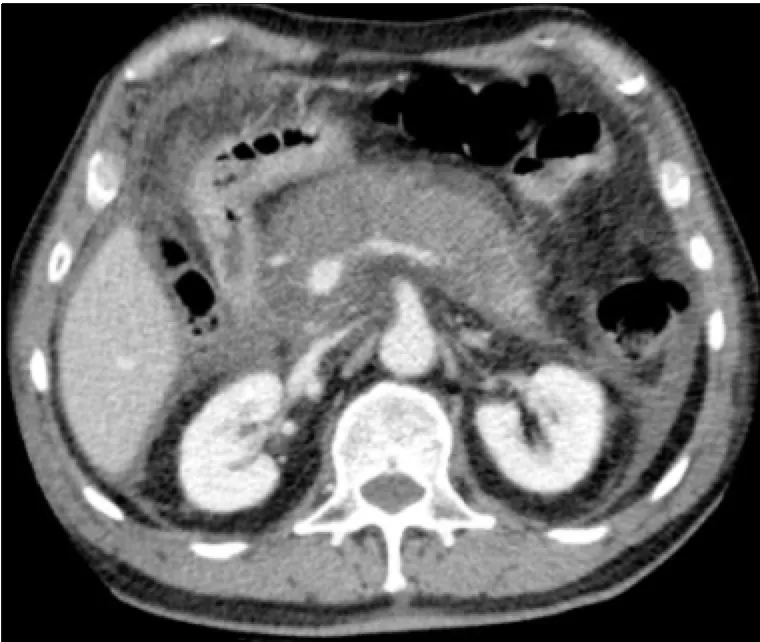

62세 남성이 상복부 통증을 호소하며 내원했다. 상복부에 압통이 있으나 반발압통은 관찰되지 않았다. 환자는 최근 10일 동안 매일 폭음했다고 한다. 혈압은 100/78 mmHg, 맥박은 110회/분, 호흡수는 22회/분, 체온은 37.5℃로 측정되었다. 혈액검사 결과와 복부 CT 사진이다. 가장 적절한 처치 방법은?

• 복부 CT 에서 pancreatic body, tail의 edematous change, pancreas 주변의 fluid collection이 관찰된다.